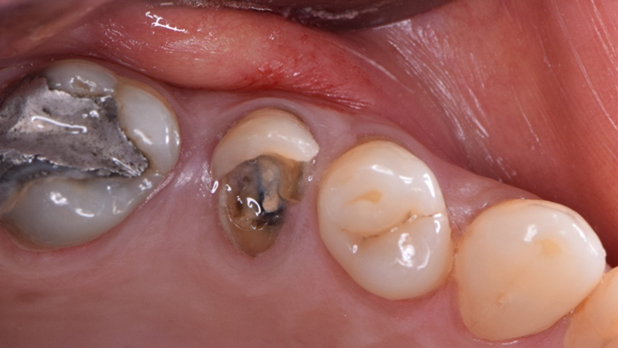

Clinical case: R2GATE GUIDE surgery with GBR

- Courtesy of Dr. Kwang Bum Park, Korea -

Dr. Kwang Bum Park, digital guided surgery, bone regeneration, maxillary posterior, #13, #14, guided surgery, GBR, AnyRidge, i-GEN, Mega-Oss, R2GATE, R2GATE Full surgical kit